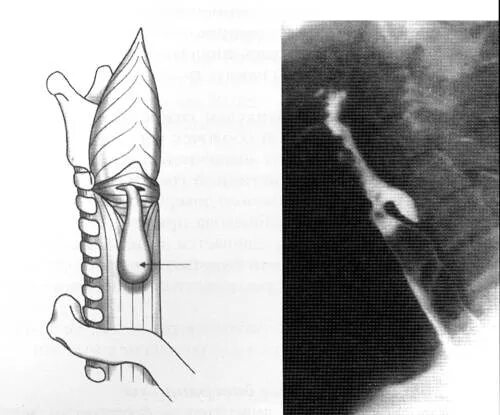

Дивертикул трахеи